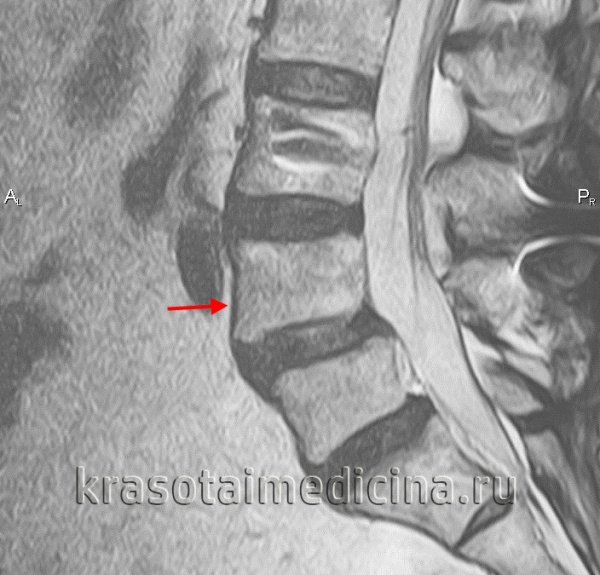

4. МРТ при спондилолизе:

• Т1-ВИ:

о Фокальное снижение интенсивности сигнала в области МЧ на сагиттальных и аксиальных изображениях

о Аналогичная картина на Т2-ВИ

• Т2-ВИ:

о Может отмечаться гиперинтенсивность сигнала в области МЧ и прилежащих участках костного мозга

• Горизонтальная ориентация межпозвонкового отверстия на сагиттальных изображениях:

о Антеролистез

о Снижение высоты диска

о Исчезновение жировой клетчатки, окружающей расположенный в отверстии корешок

(Слева) Т1-ВИ, сагиттальная проекция: несвежий дефект межсуставной части дуги, характеризующийся нормальным сигналом жировой ткани костного мозга. На уровне L5-S1 видны признаки выраженного фораминального стеноза. Обратите внимание на нормальный низкоинтенсивный сигнал интактной межсуставной части дуги L4, зона которого может напоминать дефект.